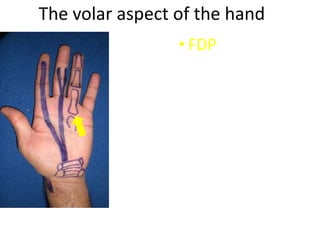

- Naming the bones, joints, tendons, nerves and skin landmarks of the hand and wrist.

- It describes flexor tendon zones, extensor compartments, and pulley system anatomy.